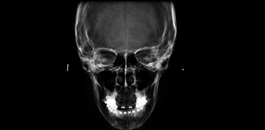

Radiografia panorâmica digital

Exame realizado em apenas 17 segundos. Nosso equipamento permite a combinação de 9 diferentes tipos de arcadas, permitindo imagens nítidas e com altíssima definição.